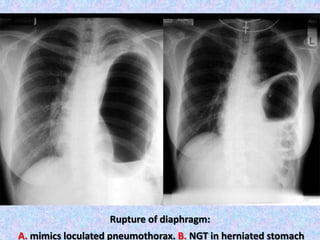

Rupture of diaphragm:

A. mimics loculated pneumothorax. B. NGT in herniated stomach